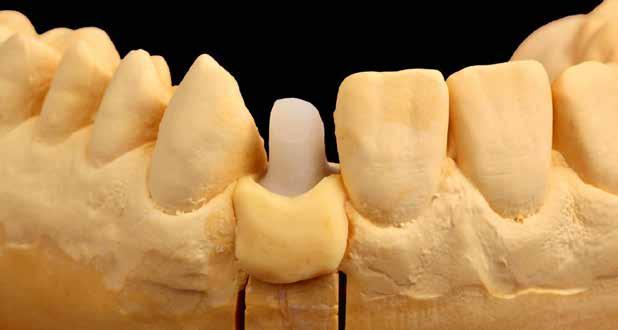

A laboratóriumokban és a fogorvosi rendelőkben mindenki ismeri ezt az esettípust: a páciensnek generalizált parodontitis miatt már több foga is elveszett a felső állcsontban, és kivehető fogsort visel. A tömörebb mandibulacsont eddig jobban bírta a krónikus bakteriális fertőzést, egészen addig, amíg a metszőfog körüli csonthiány túl nagy lett, és a metszőfogat is ki kellett húzni. Ennek az egyetlen résnek köszönhetően a páciens fix restaurációt kért. Az implantátum nem volt kívánatos, és nem is javasolt a krónikus fertőzés, a rossz csontozat és a korlátozott hely miatt. A következő esetpéldában dr. Julio Gomez Paris (Rosario, Argentína), aki fogorvos és fogtechnikus egyben, bemutatja, hogyan lehet ez a fajta eset minimálisan invazív, esztétikus és gazdaságosan megoldható a fogszín szisztematikus és precíz, a VITA 3D-MASTER fogszínkulcs segítségével történő meghatározásával és a hozzáillő VITA YZ ST Multicolor cirkon anyagának használatával (VITA Zahnfabrik, Bad Säckingen Németország).

A 76 éves páciens azért kereste fel a fogorvosi rendelőt, mert észrevette, hogy a 31-es fog kilazult, és az azzal való harapás fájdalmat okozott. Parodontális szondázás és röntgen diagnosztika után egyértelmű volt, hogy a fogat nem érdemes

4. ábra: A 32, 41 és 42 fogak előkészítése hídpillérekként.

megőrizni. Helyi érzéstelenítést követően a fogat eltávolítottuk, és a 42, 41, illetve 42 fogak között keletkezett foghiányt híd megoldással teveztük megoldani a gyógyulási folyamat után. A pontos fogszínmeghatározást és dokumentálást a VITA Linearguide 3D-MASTER segítségével végeztük el annak érdekében, hogy a megfelelő árnyalatú cirkontömböt tudjuk kiválasztani. A fogszínkulcs lehetővé teszi a szisztematikus és gyors fogszínmeghatározást két lépésben. Minden fogszín a világossági értékből, az árnyalatintenzitásból és a színárnyalatból tevődik össze. Emiatt a VITA Valueguide 3D-MASTER segítségével először csak a fogak világosságát, azaz fekete/fehér tulajdonságát állapítjuk meg. A 0-tól 5-ig

terjedő skálán a választás a 2-es árnyalatot mutató pálcára esett, tehát a VITA Chroma/Hueguide 3D Master 2-es csoportban folytattuk a meghatározást. A színárnyalattal (M) és az árnyalatintenzitással (3) kölcsönhatásban végül egy 2M3 fogszín került meghatározásra és fotódokumentálásra.

Cirkónium minden indikációhoz

A VITA YZ cirkon négy áttetszőségi fokozatban kapható (transzlucens, erősen transzlucens, szuper transz -

5. ábra: A monolitikus híd szinterezés után a kiegészítő kontroll modellen.

lucens és extra transzlucens). A szuper transzlucens, illetve polikromatikus, azaz színátmenetes VITA YZ ST Multicolor cirkont választottuk a teljes anatómikus hídpótláshoz, 1200 MPa 3 pontos hajlítószilárdsági értéke miatt kiválóan alkalmazható hidak készítéséhez. 46%-os áttetszőségével megfelel az anterior fogrégió esztétikai követelményeinek is. Az integrált színátmenetnek és a VITA fogszínkulcshoz való árnyalathűségnek köszönhetően az anyag különösen alkalmas monolitikus helyreállításra is.

2. Az előkészítést, majd a CEREC Primescan készülékkel történt digitális lenyomatvételt követően a hidat az elvárt erősségű összekötésekkel az inLab 22.0 tervező szoftverrel megterveztük és a CEREC Primemill maró készülékkel legyártottuk (all Dentsply Sirona, Bensheim Germany).

A marás után a restaurációt a VITA ZYRCOMAT 6100 MS (VITA Zahnfabrik) szinterező kemencében fejeztük be.